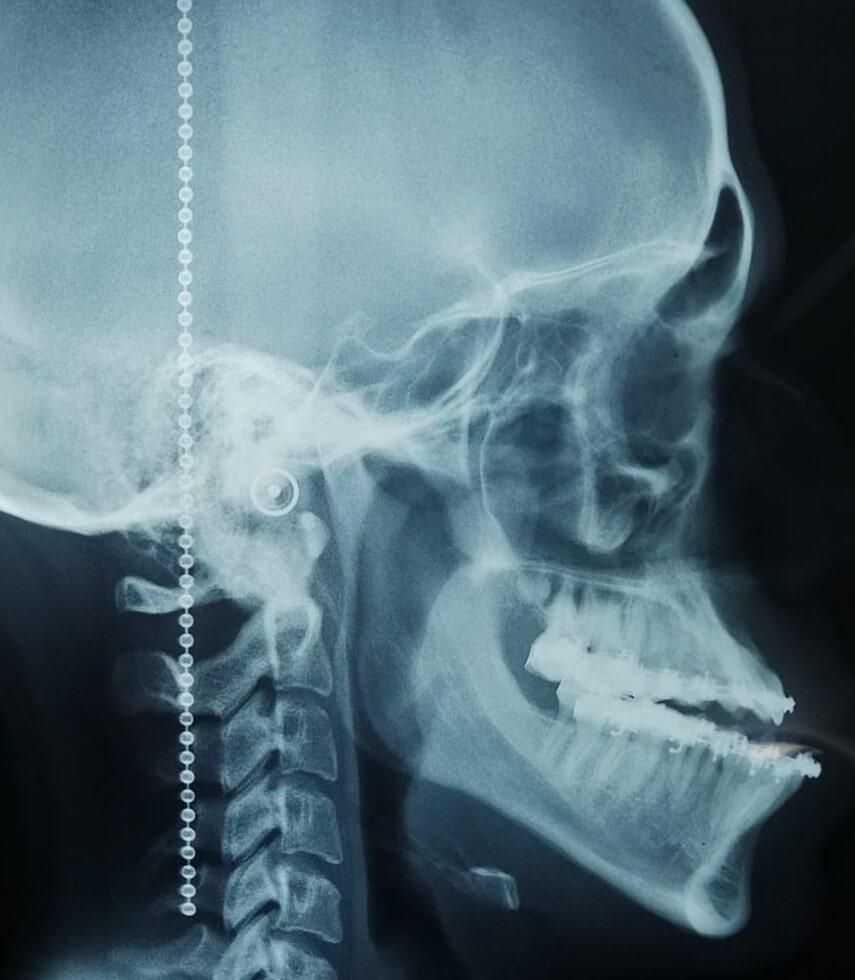

Procedimientos quirúrgicos que son utilizados para corrección de trastornos en relación maxilomandibular, como reducción de prognatismo o retrognatismo mandibular y/o maxilar, mentoplastia de avance, retroceso y ascenso o descenso, los cuales generan un cambio tanto estético como funcional en los pacientes.

La cirugía tiene una duración de 3 horas aproximadamente, todas las incisiones son intraorales, evitando dejar alguna cicatriz visible en tu cara